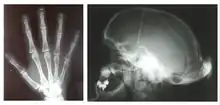

Hajdu–Cheney syndrome, also called acroosteolysis with osteoporosis and changes in skull and mandible, arthrodentoosteodysplasia and Cheney syndrome,[1] is an extremely rare autosomal dominant congenital disorder[2][3] of the connective tissue characterized by severe and excessive bone resorption leading to osteoporosis and a wide range of other possible symptoms. Mutations in the NOTCH2 gene, identified in 2011, cause HCS. HCS is so rare that only about 50 cases have been reported worldwide since the discovery of the syndrome in 1948[4]

Hajdu–Cheney syndrome causes many issues with an individual's connective tissues. Some general characteristics of an individual with Hajdu–Cheney syndrome include bone flexibility and deformities, short stature, delayed acquisition of speech and motor skills, dolichocephalic skull, Wormian bone, small maxilla, hypoplastic frontal sinuses, basilar impression, joint laxity, bulbous finger tips and severe osteoporosis. Wormian bone occurs when extra bones appear between cranial sutures. Fetuses with Hajdu–Cheney syndrome often will not be seen to unclench their hands on obstetrical ultrasound. They may also have low-set ears and their eyes may be farther apart than on a usual child, called hypertelorism. Children's heads can have some deformities in their shape and size (plagiocephaly). Early tooth loss and bone deformities, such as serpentine tibiae and fibulae, are also common in those affected.